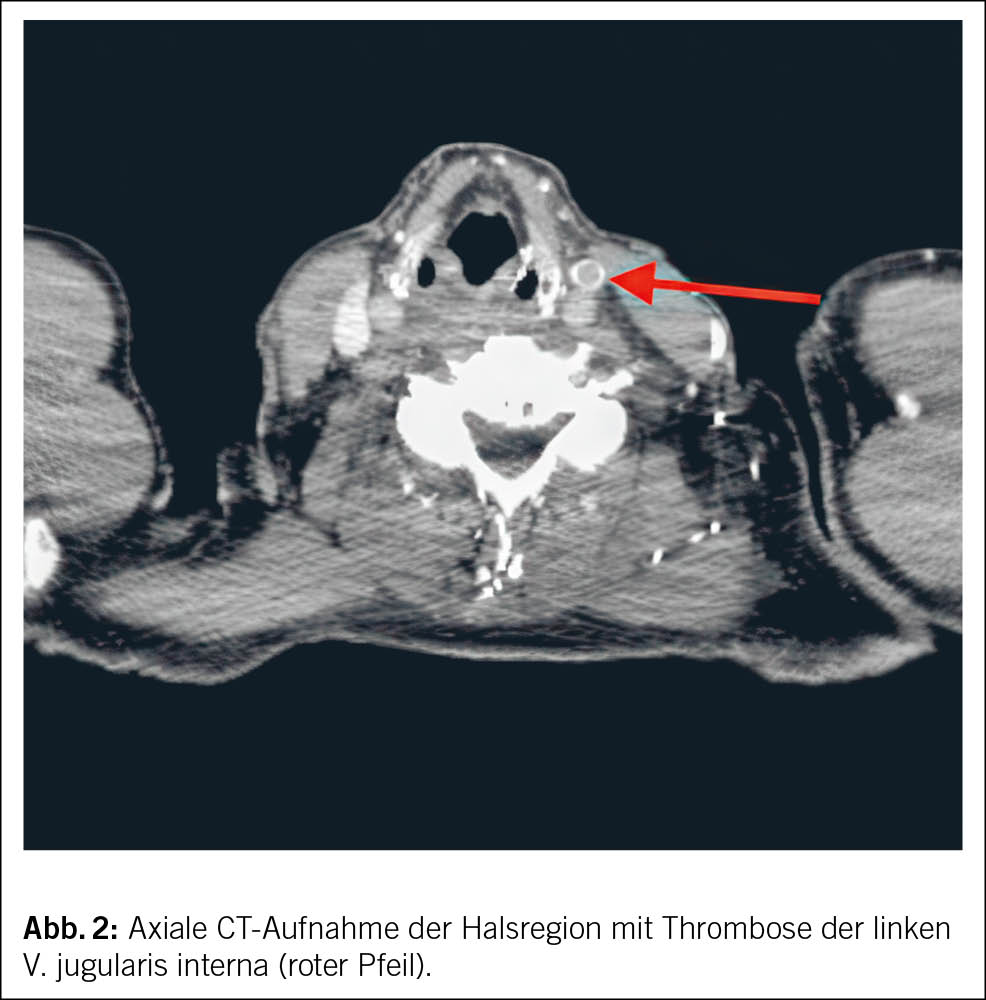

Aufgrund des Verdachts auf eine TVT der Vena jugularis erfolgte eine CT-Bildgebung der Hals- und Thoraxregion mit venöser Kontrastmittelphase. Die CT-Untersuchung bestätigte die Diagnose einer Thrombose im distalen Abschnitt der V. jugularis interna links. Zusätzlich wurde eine TVT der V. subclavia links, der V. axillaris links sowie der V. brachiocephalica links nachgewiesen, ohne Anhaltspunkte einer externen Kompression (Abb. 2 und Abb. 3).